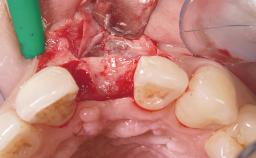

Bone Augmentation Horizontal|Simultaneous

Augmentation Materials Xenogenous|Membrane

Soft Tissue Grafting Simultaneous

Soft Tissue Anatomy Intact Defective

Soft Tissue Contour and Volume Slightly compromised